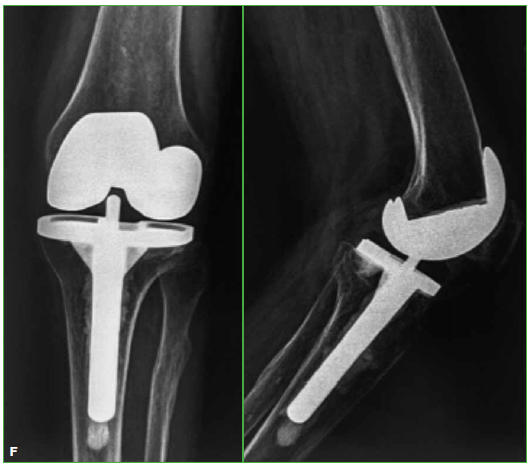

aterials and Methods: We carried out an observational, retrospective study on TKA patients treated between May 1999 and January 2013. We evaluated 25 TKAs, performed on 24 patients, with knee fracture sequela, with an average follow-up of 6.1 years and an average age of 67.1 years. Three cases (12%) had required additional surgeries before TKA. Eight cases (32%) were 2-stage surgeries. Constrained implants were used in four cases (16%). The Knee Society Score (KSS), the Functional KSS (KSSf) and the Range of Motion (ROM) were evaluated preoperatively and at the last follow-up. Prosthesis survival evaluation was documented.

Results: KSS increased from a preoperative average of 38.5 to a postoperative average of 82.8. Postoperative KSSf increased on average from 48 to 85. ROM increased on average from 7.5°-76° to 1°-102.4°. Four patients required a second surgical procedure. Prosthesis survival was 92% at a 6.1-year average follow-up.

Conclusion: TKA is an appropriate treatment for advanced PTOA, with good mid-term outcomes. If adequate postoperative alignment and correct component positioning is achieved, expected outcomes are satisfactory and similar to those with TKA in primary osteoarthritis.